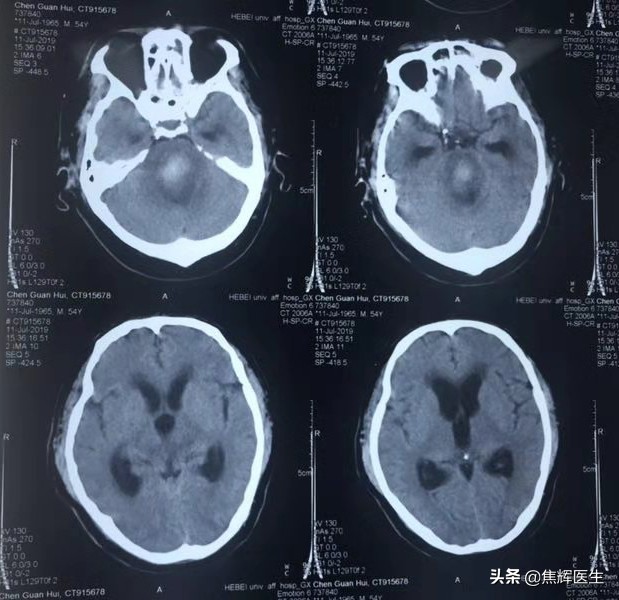

患者陈某某,男性,54岁,于2019年6月22日晚8点在家昏迷,当地医院诊断脑干出血。

患者儿子7月27日到北京天坛普华医院找到我,我建议做穿刺后微创分流术,因为患者在当地医院穿刺三次,脑压超过正常范围250~300毫米水柱,我认为脑干出血的患者脑压高,脑水肿持续时间很长,不是过去认为经过脱水治疗可以把脑压暂时降低,另外很多人学术上认为昏迷患者脑水肿靠自己吸收是可以的,但是我认为昏迷患者脑水肿即便自己吸收,是相当慢的过程,一延误就是几个月过去了,脑室扩大不说,还不容易苏醒,我经过临床研究发现,早期穿刺减压可以快速降低脑水肿,患者清醒较快。但是清醒后颅内压不是恒定不变的,它会不断的动态变化,如果脑压不稳,二次出血、三次出血就会发生,严重威胁患者的生命和生活质量,还会给患者及家属带来精神紧张情绪,总怕再次出血。